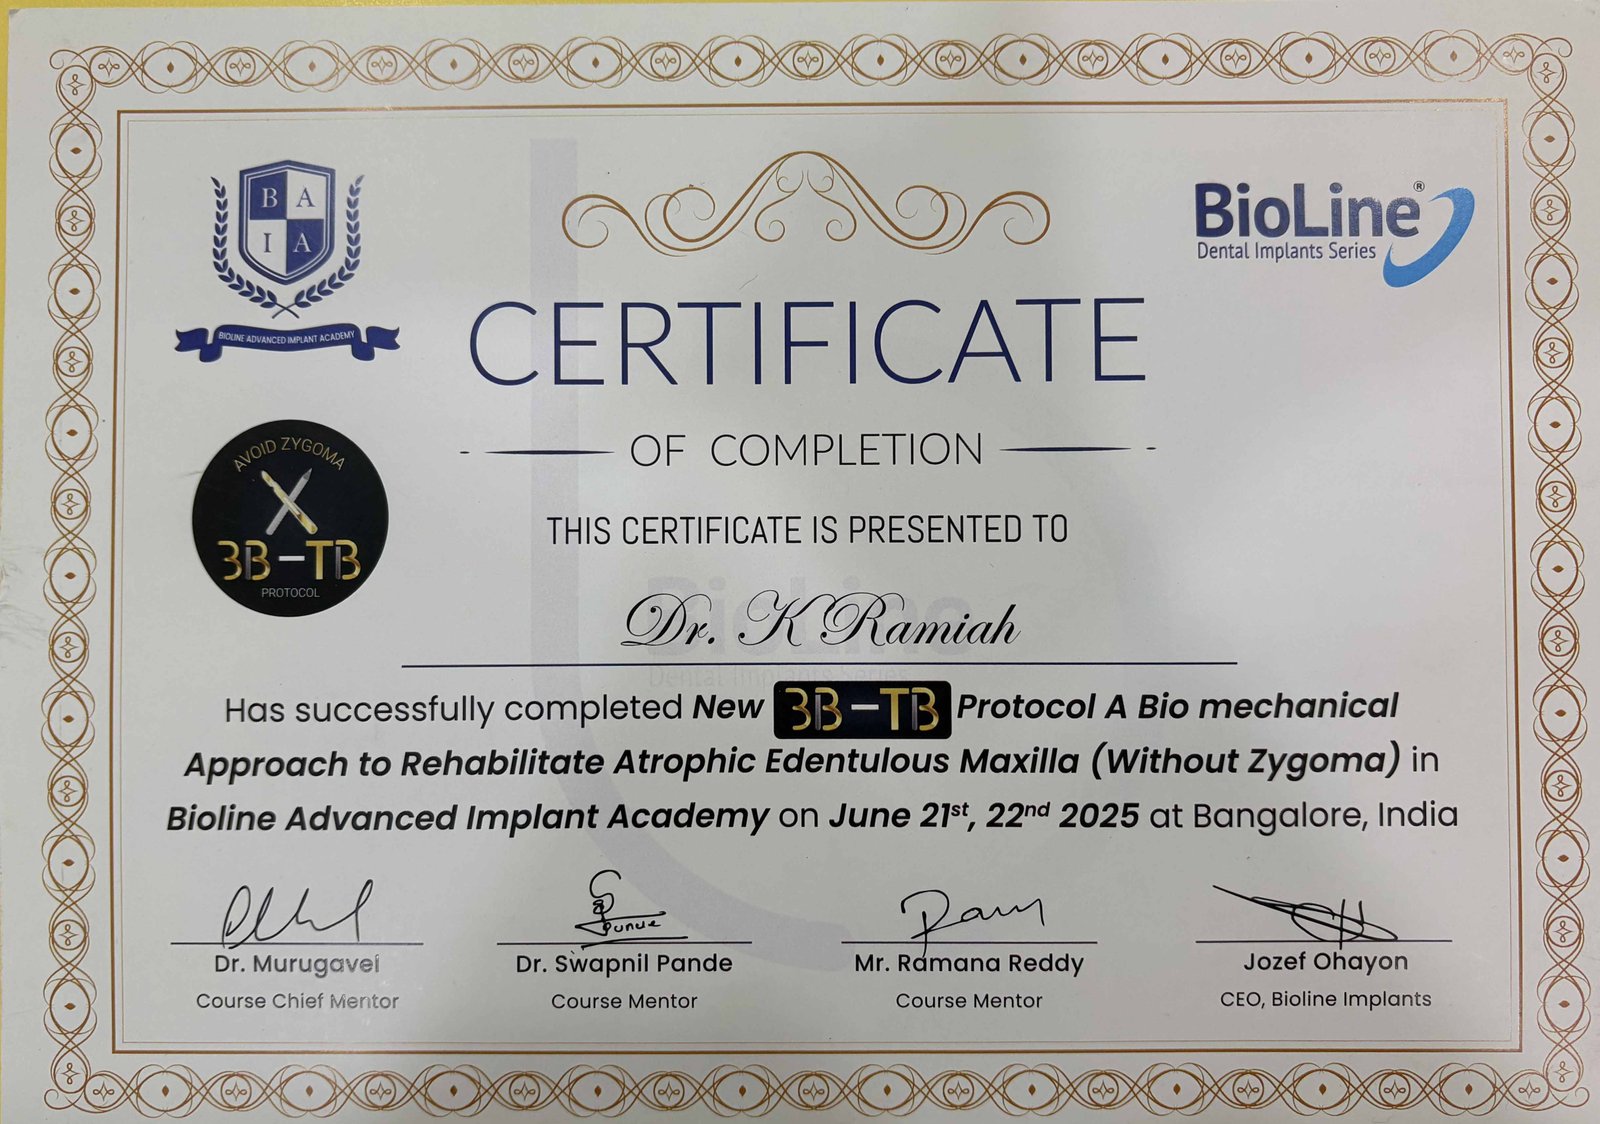

We started our journey in 2021 with a single dental chair and a strong commitment to providing quality dental care. With over 5 years of professional experience, our practice has grown steadily and now operates with three fully equipped dental chairs to serve our patients better. Having completed an MS in Italy, we bring advanced knowledge and global expertise to our treatments, with a special focus on implantology. Over the years, we have successfully handled more than 30,000 consultations and built a community of over 3,000 happy clients, reflecting our dedication to excellence, precision, and patient satisfaction.

Advanced credentials and clinical recognitions